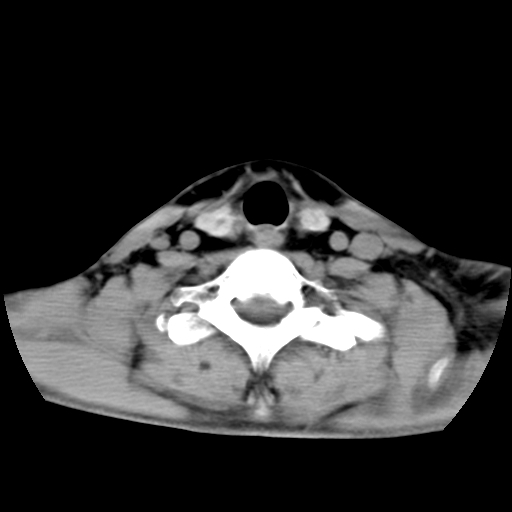

标题: CT24019:男,45岁,发现颈部肿物5个月。 [打印本页]

男,45岁,发现颈部肿物5个月,彩超示:双侧颈部及下颌部软组织增厚。

考虑双侧颈项部良性对称性脂肪增多症。